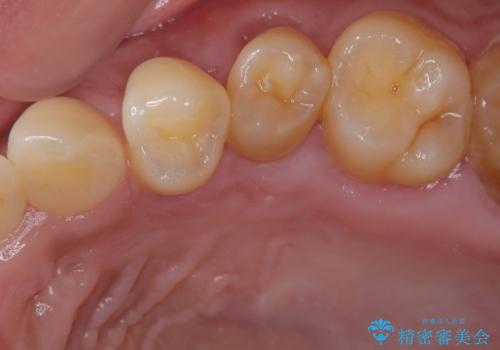

- 食いしばりと強いブラッシングにより、上顎小臼歯2本に知覚過敏を感じるようになったとのことで来院された患者様です。

歯肉退縮により歯根部が露出し、冷たい飲み物に痛みを感じる状態でした。

根面被覆を目的として歯肉移植術を行うこととしました。